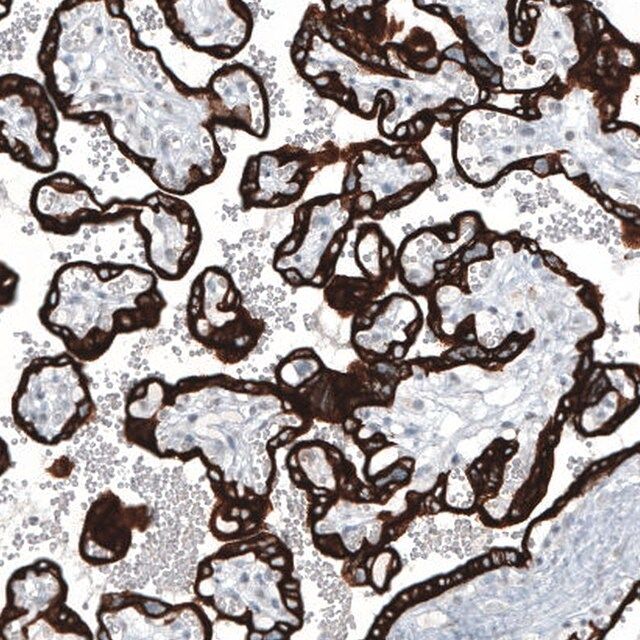

All Prestige Antibodies Powered by Atlas Antibodies are developed and validated by the Human Protein Atlas (HPA) project (www.proteinatlas.org)and as a result, are supported by the most extensive characterization in the industry. The Human Protein Atlas project can be subdivided into three efforts: Human Tissue Atlas, Cancer Atlas, and Human Cell Atlas. The antibodies that have been generated in support of the Tissue and Cancer Atlas projects have been tested by immunohistochemistry against hundreds of normal and disease tissues and through the recent efforts of the Human Cell Atlas project, many have been characterized by immunofluorescence to map the human proteome not only at the tissue level but now at the subcellular level. These images and the collecation of this vast data set can be viewed on the Human Protein Atlas (HPA) site by clicking on the Image Gallery link. To view these protocols and other useful information about Prestige Antibodies and the HPA, visit sigma.com/prestige.

- IHC tissue array of 44 normal human tissues and 20 of the most common cancer type tissues.

| technique(s) | immunohistochemistry: 1:500-1:1000 western blot: 1 μg/mL |